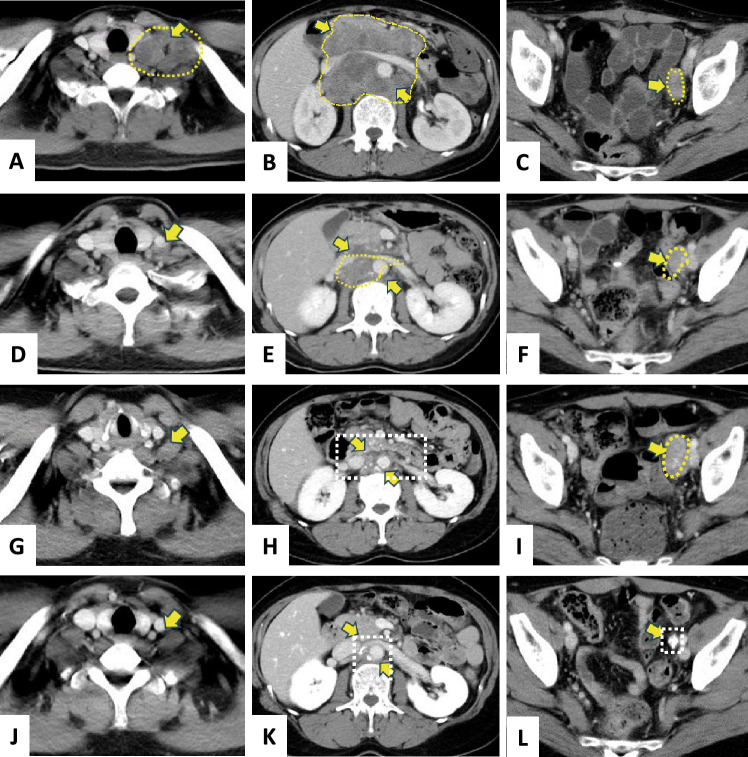

The immune checkpoint system suppresses T-cell activity. Unlike cytotoxic anticancer drugs that directly kill cells, immune checkpoint inhibitors (ICIs) are generally safer by stimulating tumor immunity. However, most clinical trials require patients to have a better performance status (PS), leaving limited evidence for those with poorer PS. In practice, patients may be classified with poor PS due to tumor-induced pain and motor dysfunction, even if major organs remain functional. Real-world data on non-small cell lung cancer has shown no safety difference between patients with PS 3/4 and those with lower PS. Approximately 20-30% of endometrial cancer cases show microsatellite instability-high (MSI-high), the highest among common malignancies. A 46-year-old patient with advanced, recurrent endometrial cancer resistant to standard chemotherapy, and PS of 4 from severe pelvic pain, was diagnosed with MSI-high. Pembrolizumab was initiated and continued for 19 courses, after which lesions had disappeared or calcified, leading to drug discontinuation. Now, 4 and a half years post-treatment, she has regained independent mobility and returned to work, and her PS has improved to approximately 1. Side effects included Grade 2 or lower thyroiditis, hypothyroidism, and hypoadrenalism, manageable with hormone replacement therapy and temporary pembrolizumab suspension. This case underscores the need to test for MSI-high/mismatch repair deficiency in endometrial cancer and to consider ICI therapy in patients with poor PS but no major organ dysfunction. In such cases, ICI can rapidly improve overall condition, a phenomenon known as a Lazarus-type response, as seen in other cancers such as non-small cell lung cancer.